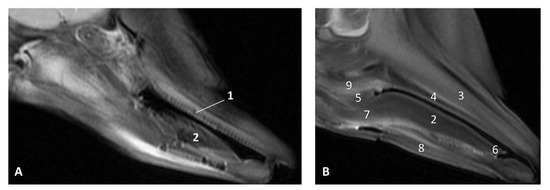

3.1.2. MRI Study

The T2 MRI image of the oral cavity in this Delphinus delphis (dde11) shows that the maxillary bone is medium hyperintense with respect to the hypointense hard palate. The superficial mucosa of tongue is slightly hyperintense with respect to the hypointense depressor, protractor and retractor muscles of the tongue. A hyperintense stratum under the tongue muscles is probably due to the high rate of irrigation of these muscles. We observed that non-erupted teeth can be seen under the gums (Figure 11).

Figure 11. Images of the oral cavity. MR sagittal images is oriented so that the rostral is to the right. (A) T2 FrFSE sagittal plane. 6 months, dde8. Image of the oral cavity. (B) T2 FrFSE sagittal plane. Quadknee coil. 8 months, dde11. 1, Teeth (under gum); 2, Tongue: body; 3, Maxillary bone; 4, Hard palate; 5, Soft palate; 6, Tongue: apex; 7, Tongue: root; 8, Mandibles; 9, Pterygoid and palatine bones.